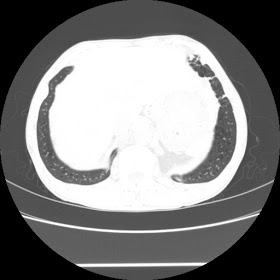

A 52 Years old man suffering with chest pain since 3 years

For seen patient record file please click here

HRCT Chest